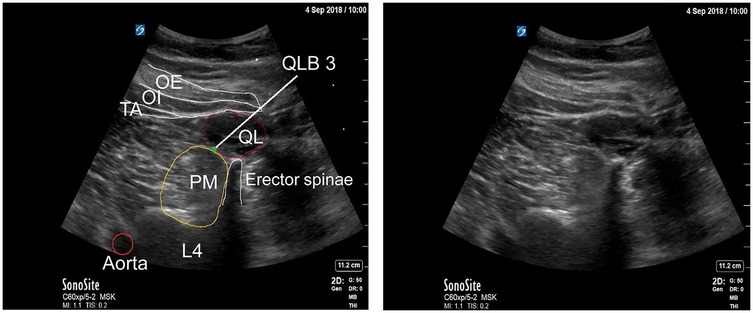

The QLB is an ultrasound-guided fascial plane technique in which local anesthetic is deposited adjacent to the QL muscle to target thoracolumbar nerves (26). The method was first described by Blanco in 2007 (27) and has since gained widespread application across multiple surgical specialties. Several approaches have been developed, each distinguished by the position of the needle relative to the QL muscle and its surrounding fascial layers (Figure 1) (28, 29). A thorough understanding of the thoracolumbar fascia (TLF) is essential for understanding the mechanisms underlying these variants (30).

Ultrasound images labeled (a) and (b) depicting anatomical structures with abbreviations. Image (a) highlights the QL muscle in brown, surrounded by structures labeled IO, TA, PM, and TP. Image (b) includes lines indicating locations such as QLB1, QLB2, IQLB, and TQLB, with labeled muscle groups QL, IO, TA, PM, ES, and TP.

Figure 1. (a) Schematic representation of the quadratus lumborum region on ultrasound. (b) Ultrasound images demonstrating four different quadratus lumborum block approaches. EO, external oblique; ES, erector spinae; IO, internal oblique; IQLB, intramuscular quadratus lumborum block; QL, quadratus lumborum; QLB1, quadratus lumborum block 1; QLB2, quadratus lumborum block 2; TA, transversus abdominis; TP, transverse process; TQLB, transmuscular quadratus lumborum block [Reproduced from Korgvee et al. (29). © Wolters Kluwer Health, Inc. Published with permission under STM Permissions Guidelines].